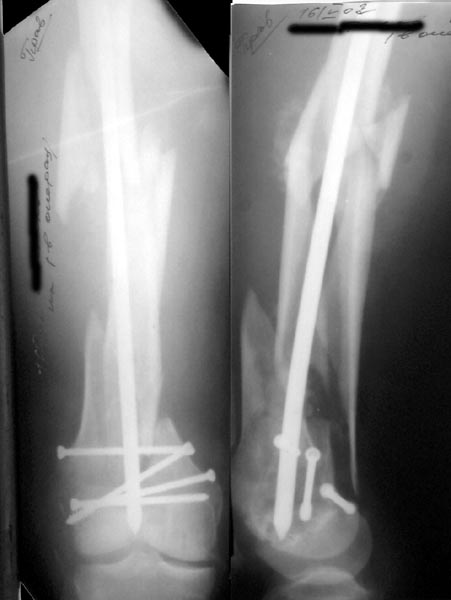

Re: Многооскольчатое бедро

Alexander Chelnokov 16 Май 2002, 17:30

А> Попробуй ретроградно интрамедуллярный гвоздь с блокированием

Нету у нас (пока?) гвоздей для ретроградного введения. Доводилось слышать, что можно любые гвозди вводить ретроградно, но как-то не

получается пока преодолеть психологический барьер. В основном потому, что не могу для себя уяснить преимущества введения через колено

обычного UFN. Или, как коллеги из Индии рассказывали, кое-кто вводит UTN в бедро ретроградно.

ЛА> и увеличенным количеством винтов дистально или как ты любишь miss

ЛА> a nail.

Да, примерно так и сделали. Надо было, пожалуй, кончик гвоздя еще спилить, чтобы отверстие было еще дистальнее. Англоязычные коллеги еще

советовали винты в передне-заднем направлении вводить, но что-то не увидел, где там подходящее место.